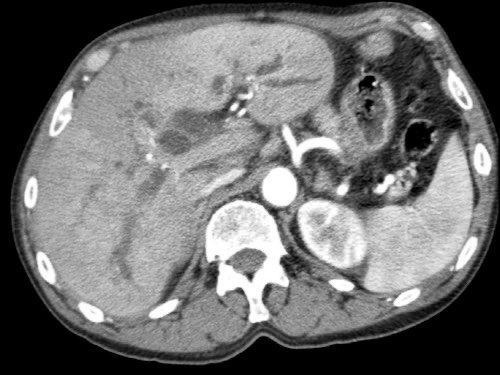

Tái tạo mặt phẳng coronal cho thấy một khối u lớn xuất phát từ cổ tụy với kiểu phát triển xâm lấn (hình A và B).

Có hiện tượng bao quanh động mạch thân tạng 360º (mũi tên trong A).

CT axial MIP tại mức động mạch thân tạng cho thấy hẹp động mạch gan chung bị bao quanh (mũi tên), rất nghi ngờ xâm lấn.